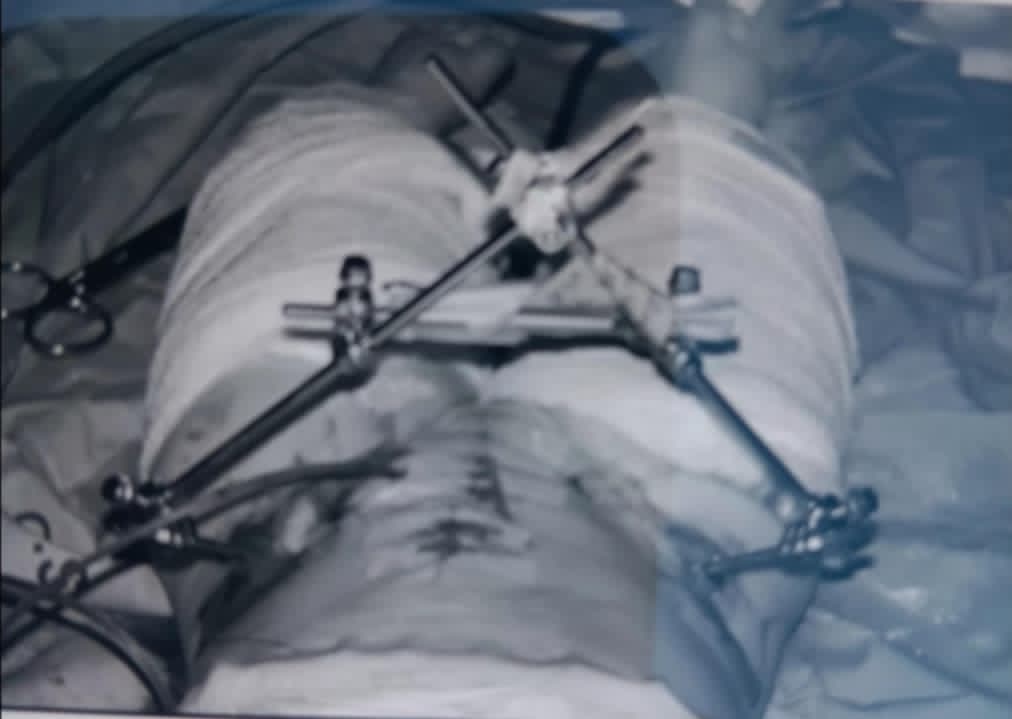

Pelvic osteotomy is a surgical procedure that involves reshaping the hip socket (acetabulum) to improve the fit and stability of the hip joint. It is primarily used to treat developmental dysplasia of the hip (DDH) and other hip joint problems that cause pain and limited mobility. The procedure aims to redirect the acetabulum to better cover and stabilize the femoral head (the ball of the hip joint), potentially preventing or delaying osteoarthritis.

April 14, 1984 I was in a body cast for 3 months I had to relearn to walk and to this day struggle with failed surgery